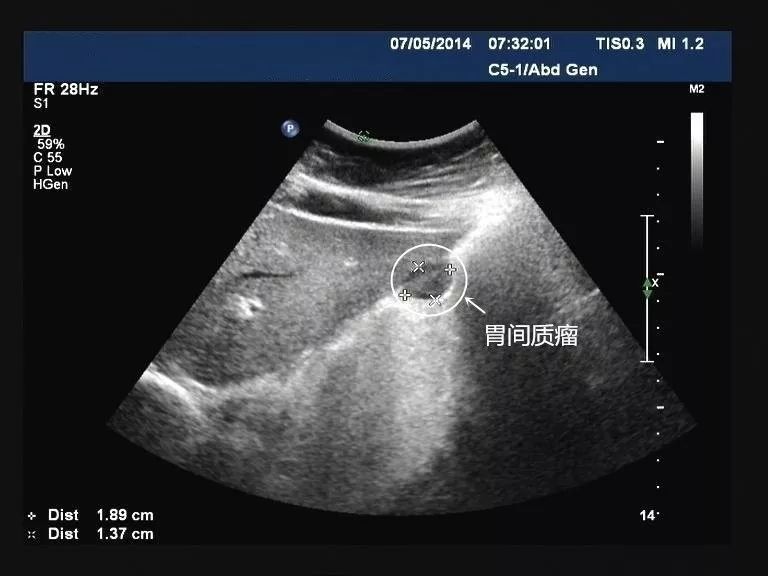

胃小弯侧间质瘤: